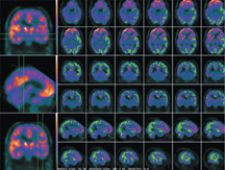

PET-MRI Fusion, Fronto-temporal Dementia.

In the last few years, fusion imaging has enabled tremendous clinical milestones, such as using PET images on patients with Alzheimer’s disease to highlight any area of the brain with high concentrations of plaques. Another technique involves ictal-interictal image abstraction overlaid on MRI to identify abnormal bloodflow in the brain due to epilepsy and for epileptic surgery. For biopsy or surgery, fusing images of PET or SPECT on MRI or CT helps localize disease and anatomically guide the surgeon, and multitrace image fusion facilitates the treatment of patients with Hodgkin’s lymphoma.

“Multimodality image fusion in the brain is relatively easy, because the organ is relatively rigid. Automatic image registration and fusion of SPECT, PET and MRI is usually very rapid and effective,” explained S. Ted Treves, M.D., chief, Division of Nuclear Medicine, vice chairman for Information Systems, department of Radiology, Children’s Hospital, professor of Radiology, Harvard Medical School. “Image fusion in the body is not as easy as in the brain as the position of the body may not be the same during the acquisition of each modality. Also, the organs within the body are nonrigid (respiratory motion, cardiac motion, etc.), making exact image registration and fusion more difficult. These limitations can be sometimes overcome by using morphing methods or manual overrides.”